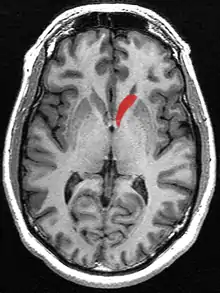

Caudate nucleus (in red) shown within the brain

The caudate nuclei are located near the center of the brain, sitting astride the thalamus. There is a caudate nucleus within each hemisphere of the brain. Individually, they resemble a C-shape structure with a wider "head" (caput in Latin) at the front, tapering to a "body" (corpus) and a "tail" (cauda). Sometimes a part of the caudate nucleus is referred to as the "knee" (genu).[7] The caudate head receives its blood supply from the lenticulostriate artery while the tail of the caudate receives its blood supply from the anterior choroidal artery.[8]